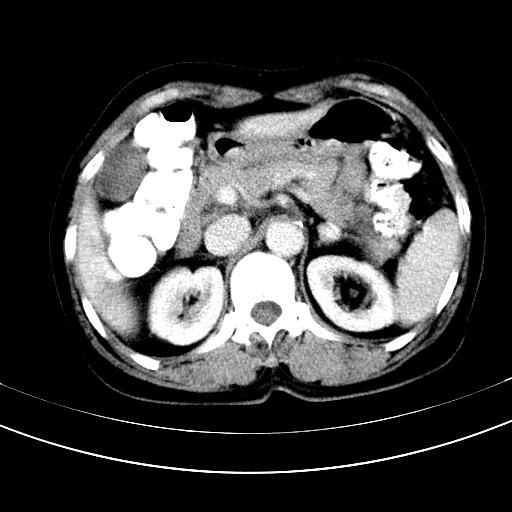

补充强化片

不强化不好说!肝内像是血管瘤,胃底考虑间质瘤。脾静脉还有曲张的可能。本病例必须强化明确!

肝左叶及尾叶低密度灶,增强有渐进性明显强化,考虑血管瘤。胃内“充缺”首先要排除异物(食物),变换体位可鉴别。增强时机抓的不好,还应该有延时像。

谢谢楼主的增强片子,平扫没发现左侧肾上腺的问题很不好意思,可惜片子只有门脉期,所以还只有猜,肝脏的病灶在门脉期部分强化,首先考虑为血管瘤(其他的用一种病不好解释)胃要喝水就好了现在不好说是否有问题,左肾上腺的问题考虑是肿瘤。

做了增强后,可以明确胃是没有肿瘤的,肾上腺也没有肿瘤.肝左叶的病灶首先考虑血管瘤,应该再延迟,肝尾状叶的病灶仍不能排除肝癌的可能性.